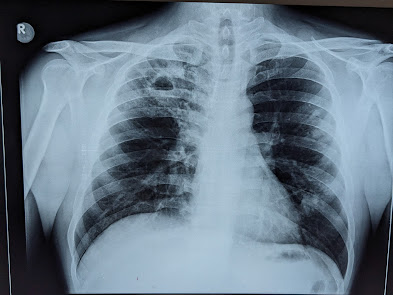

Tuberculosis